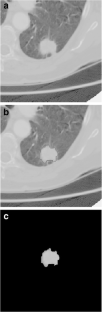

Fig. 1